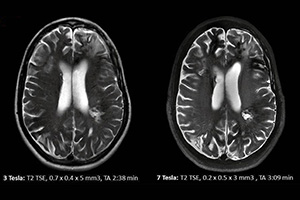

Since 1993, Star Test Diagnosis and Imaging Center has been put into service with the aim of reaching higher quality service, more satisfied